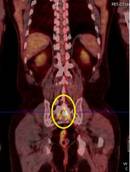

Ca lâm sàng 3: Bệnh nhân Nguyễn X.T., nam, 58 tuổi. Chẩn đoán: U lympho ác tính không Hodgkin, GPB: WF6. Hình PET cho thấy tổn thương ở phổi, hạch, xương, tuyến thượng thận hai bên (mũi tên). Hình CT và PET/CT cho thấy tổn thương tăng hấp thu FDG tại vị trí tuyến thượng thận hai bên (mũi tên).